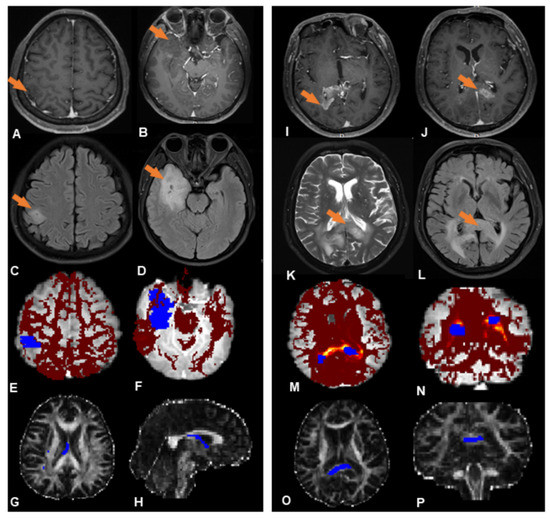

3.2. Probabilistic Fiber Tracking